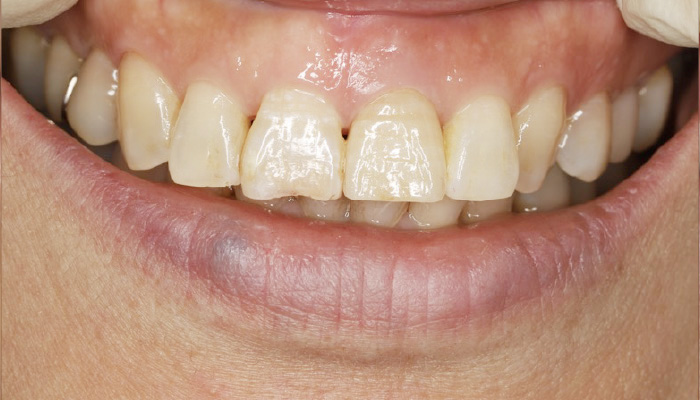

症例 1

治療前

治療後

| 主訴 | 前歯をきれいにしたい |

| 先生からの提案 (治療内容について) |

全体的に歯の色が変色しています。もし全体的に白くするならホワイトニング、矯正、ラミネートべニアの治療が必要と説明しました。 患者さんと相談の上、今の歯にあわせる自然美を希望されました。 |

| 治療期間 | 1か月 |

| 治療費 | 165,000円 |

| 治療のリスク | セラミックスの欠けは起こる可能性がある。 |